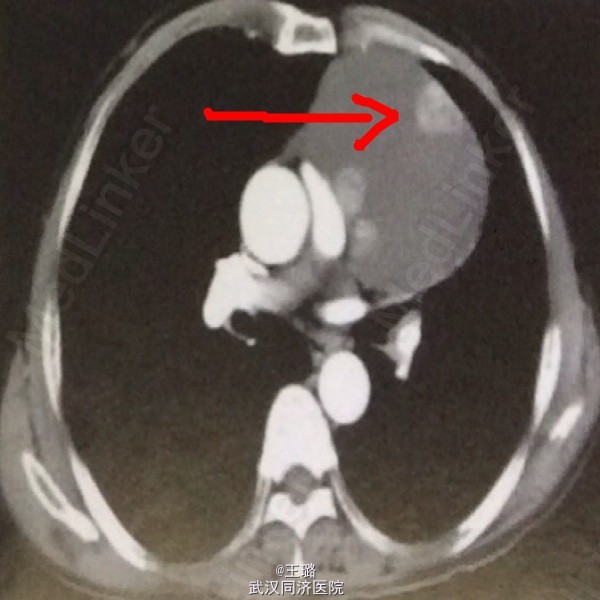

患者,男,63岁,胸闷一星期加重两天入院。体格检查:两肺呼吸音稍粗,未闻及干湿啰音。实验室检查:中性粒细胞增高,淋巴细胞降低,其余无异常。CT示:前纵隔左侧出现类圆形囊性病灶,边缘可见实性结节。MPR示:囊性占位内可见细条状分隔,囊肿与周围结构界限清晰。遂给予手术切除,术后病检示:多房性胸腺囊肿。胸腺囊肿为纵隔良性肿瘤,较少见,若囊肿破溃穿入心包可引起心包填塞。